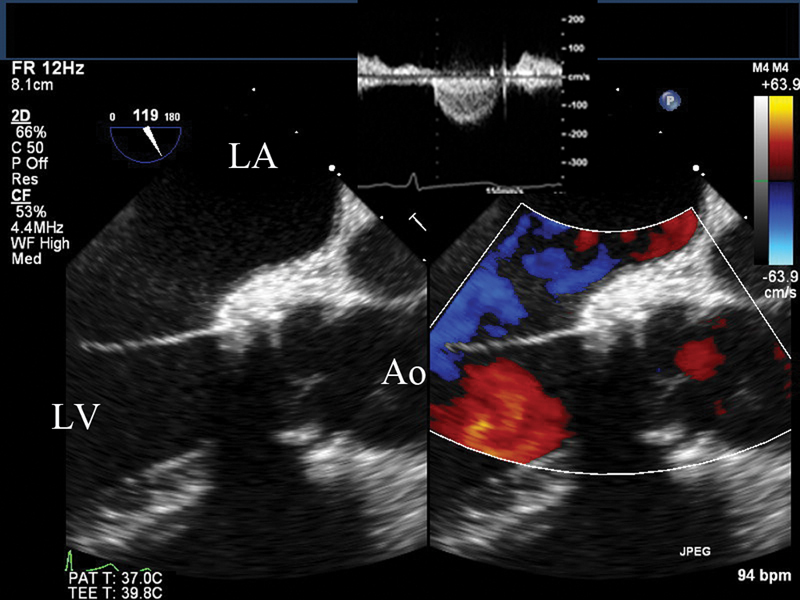

فحوصات تشخيصية لبعض امراض القلب والشرايين التاجية